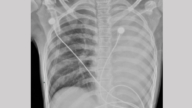

中國「流感」傳播迅猛,各地不斷傳出因學生大面積感染流感而停課的消息。11月21日,中共疾病預防控制中心人員在記者會上向媒體介紹流感疫情時稱:當前,主要流行株是甲型H3N2亞型,但也有甲型H1N1亞型和B型流感共同流行。

在11月10日至16日這一週內,全國至少發生了955起「流感樣病例爆發疫情」,而且各地的流感活動還在上升,疫情目前已進入快速上升期。

監測數據顯示,確診的流感病毒感染案例中,99.1%為甲型流感。

不過,來自民間的消息顯示,大陸各地疫情蔓延的狀況,比中共官方所描述的情況更加嚴重。